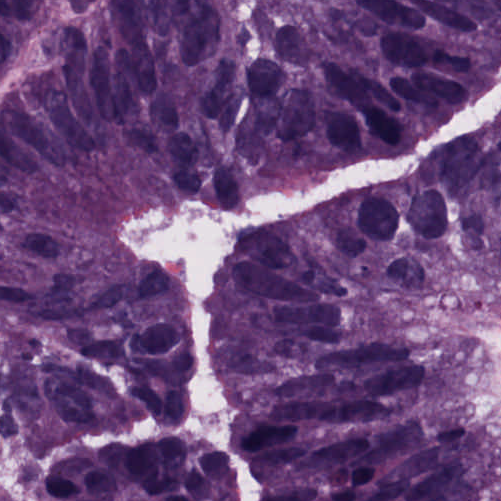

As an essential part of digital pathology, histopathology image analysis is playing increasingly important role in cancer diagnosis, which can provide direct and reliable evidence to diagnose the grade and type of cancer. This paper deals with nuclei segmentation, an important step in histopathological image analysis. The purpose of nuclei semgentation is not only counting the number of nuclei but also obtaining the detailed information of each nucleus. So unlike nuclei detection, here the outputs are the contour of each nucleus instead of only the position of their central points. Hence we can exactly extract each nucleus from the image and make it available for further analysis. For example, the features of the individual nucleus and the distribution of nuclei clusters can be used to grade and classify status of breast cancers [3, 4]. Because of appearance variation such as color, shape, and texture, nuclei segmentation from histopathological images could be very challenging, as illustrated in Fig.1, in which it is very challenging even for human to recognize and segment all nuclei within the images. Fig.1(a) and Fig.1(b) illustrate two histopathological images from different organs. Fig.1(c) and Fig.1(d) are two histopathological images from same organ but have different cancer grade.